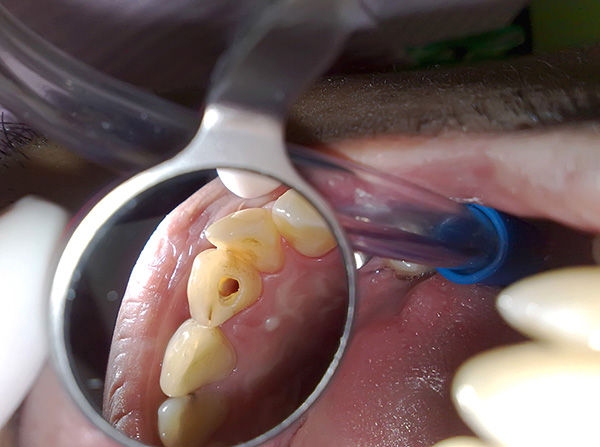

A foto a seguir mostra um chip de ferramenta extraído do canal radicular:

No entanto, ainda é necessário obter o chip, porque a parte da ferramenta que permanece no canal bloqueia um determinado segmento da raiz e não permite que seu processamento seja concluído - portanto, um foco de infecção não tratado é formado, o que no futuro pode levar à extração dentária.